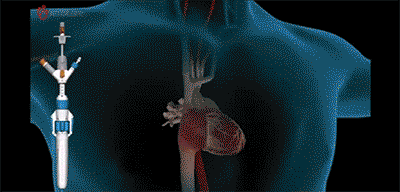

三例患者均在全身麻醉下穿刺右侧颈静脉建立手术入路,在X线及超声引导下,将输送系统送到右心房,通过调整弯度,顺利跨过三尖瓣口进入右心室,释放夹持件,使其固定在三尖瓣前瓣,再通过藏针将锚定件固定在室间隔,最后撤出输送系统,完成LuX-Valve Plus人工三尖瓣瓣膜的植入。

演示视频LuX-Valve经导管三尖瓣置换系统在国际上率先采用“非径向支撑力”和“室间隔固定”设计理念,可更好适应三尖瓣结构,减少并发症,是我国拥有完全自主知识产权的心脏瓣膜介入器械。LuX-Valve Plus是LuX-Valve第二代产品,采用经颈静脉入路,可通过穿刺建立入路,实现完全介入治疗,进一步减小损伤。